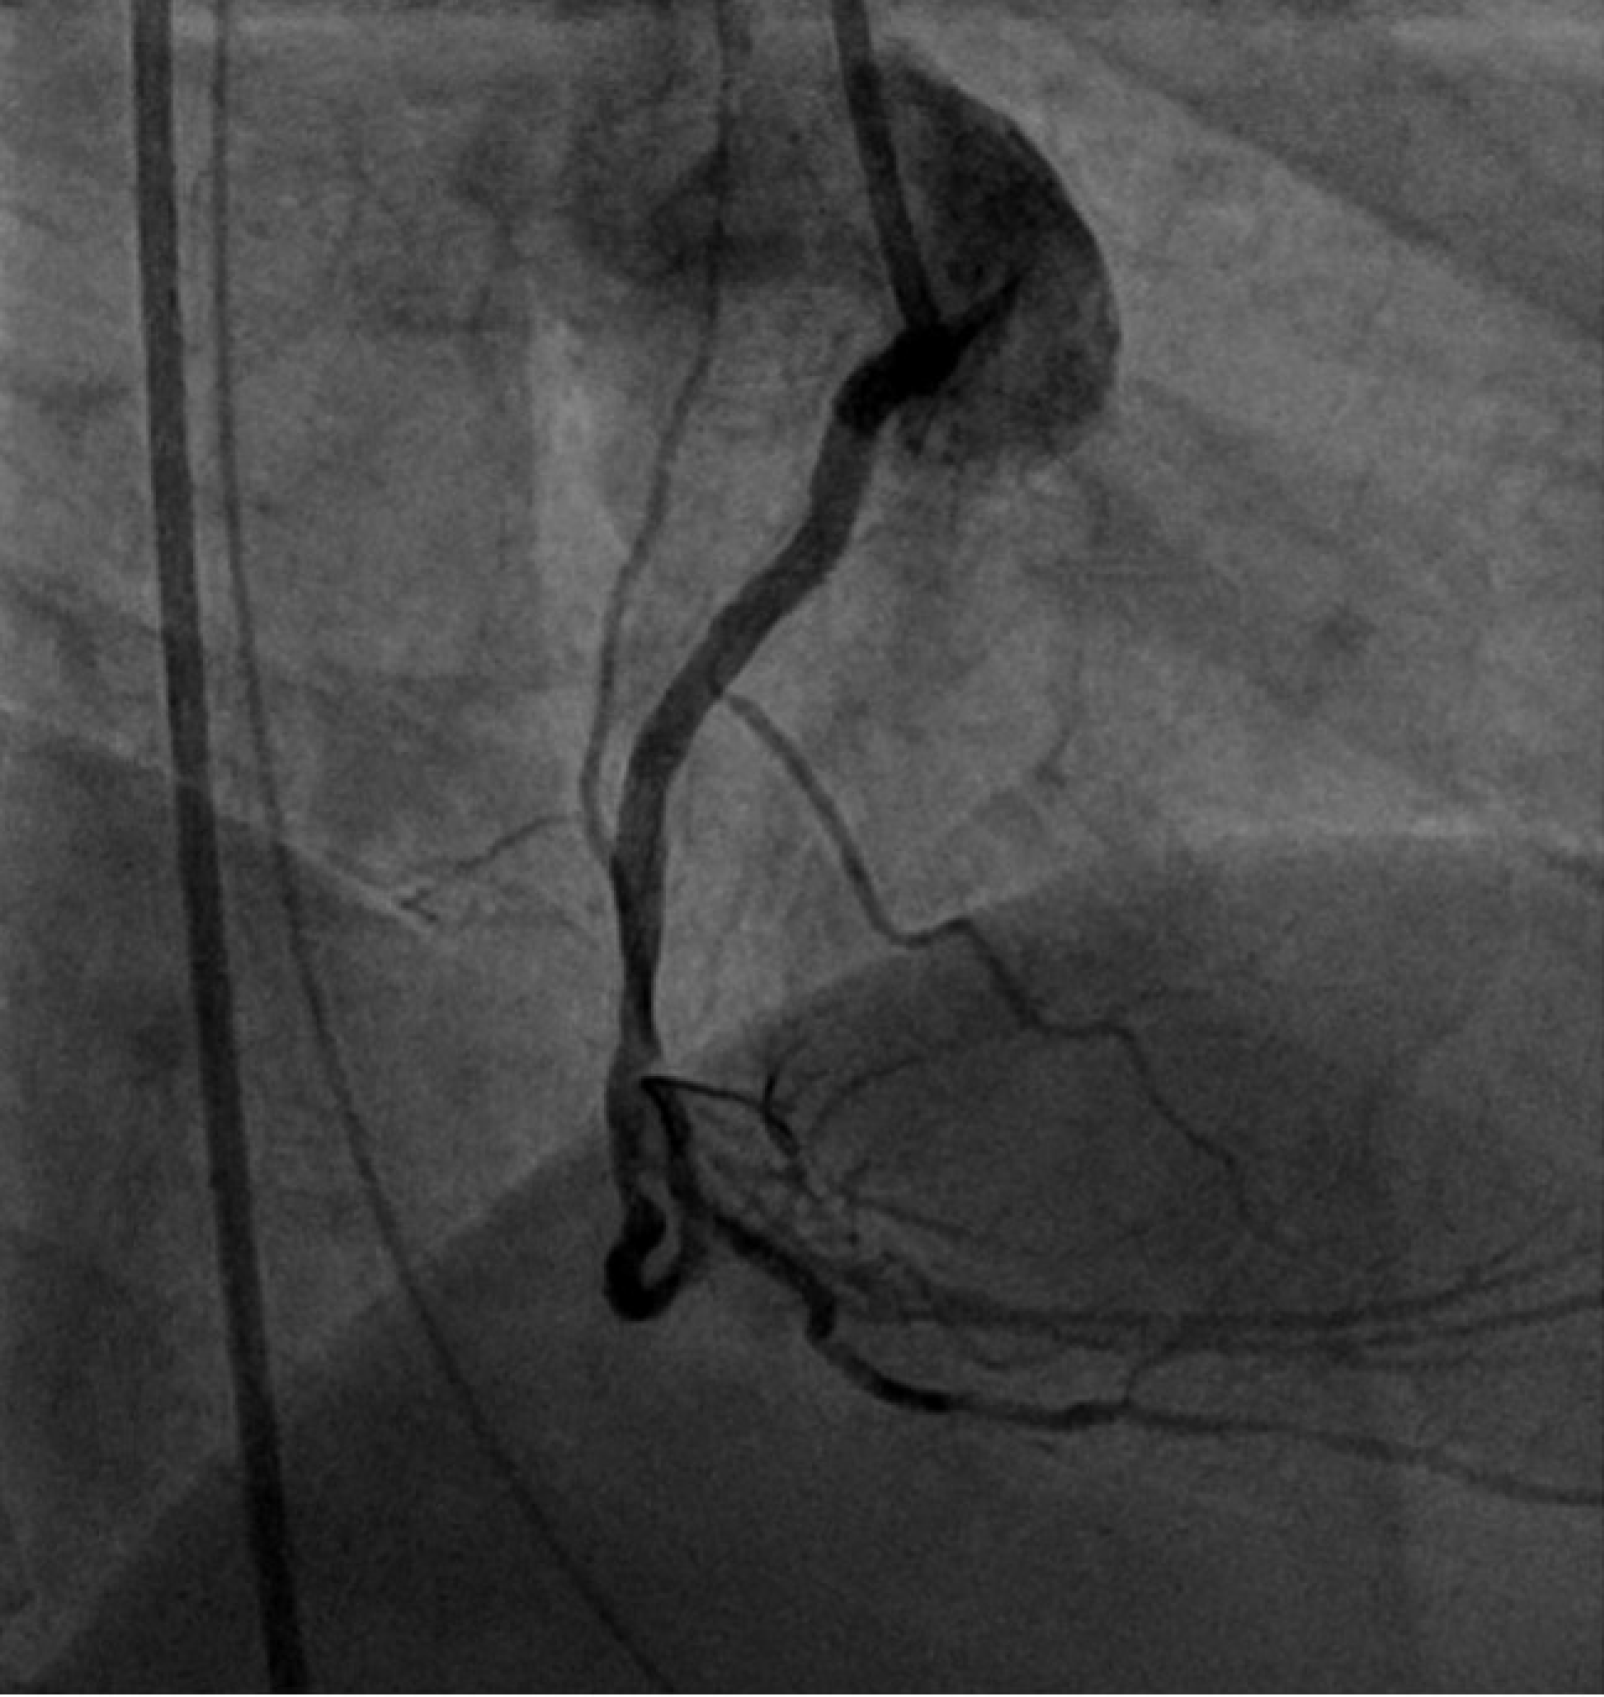

Figure 2 Initial coronary angiogram images prior to percutaneous coronary intervention showing a completely occluded right coronary artery with thrombolysis in myocardial infarction Grade 1 flow (orange arrow).